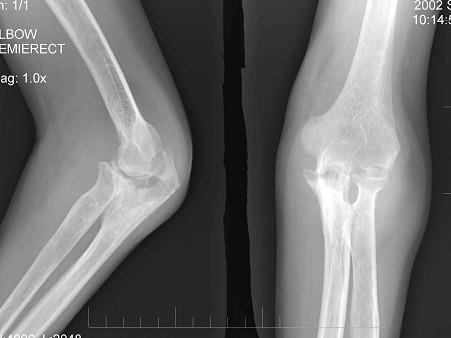

问题 男性患者,有低烧,消廋,胸片示有结核病灶,请结合所提供图像,选择最佳选项 ( )

选项 A、未见异常 B、类风湿关节炎 C、肘关节退行性变 D、骨折 E、肘关节结核

答案 E